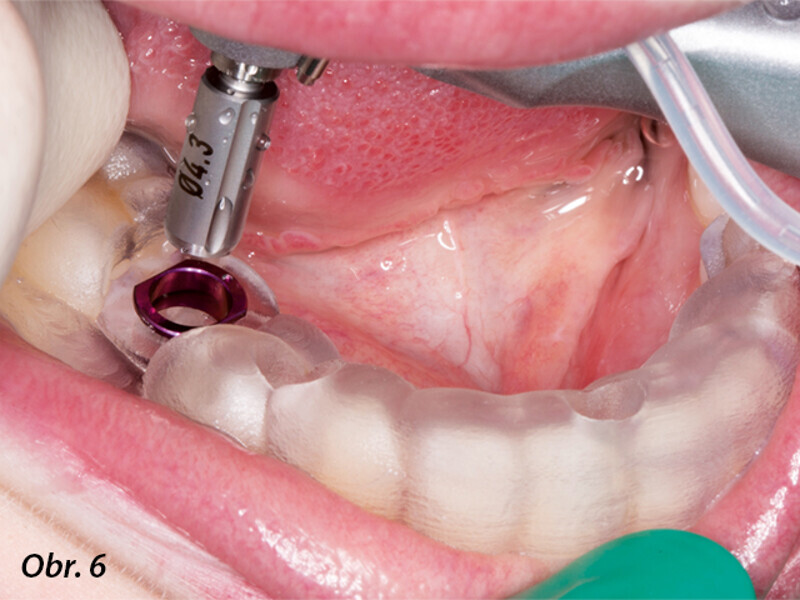

Řízená implantologie za použití řešení Planmeca all-in-one